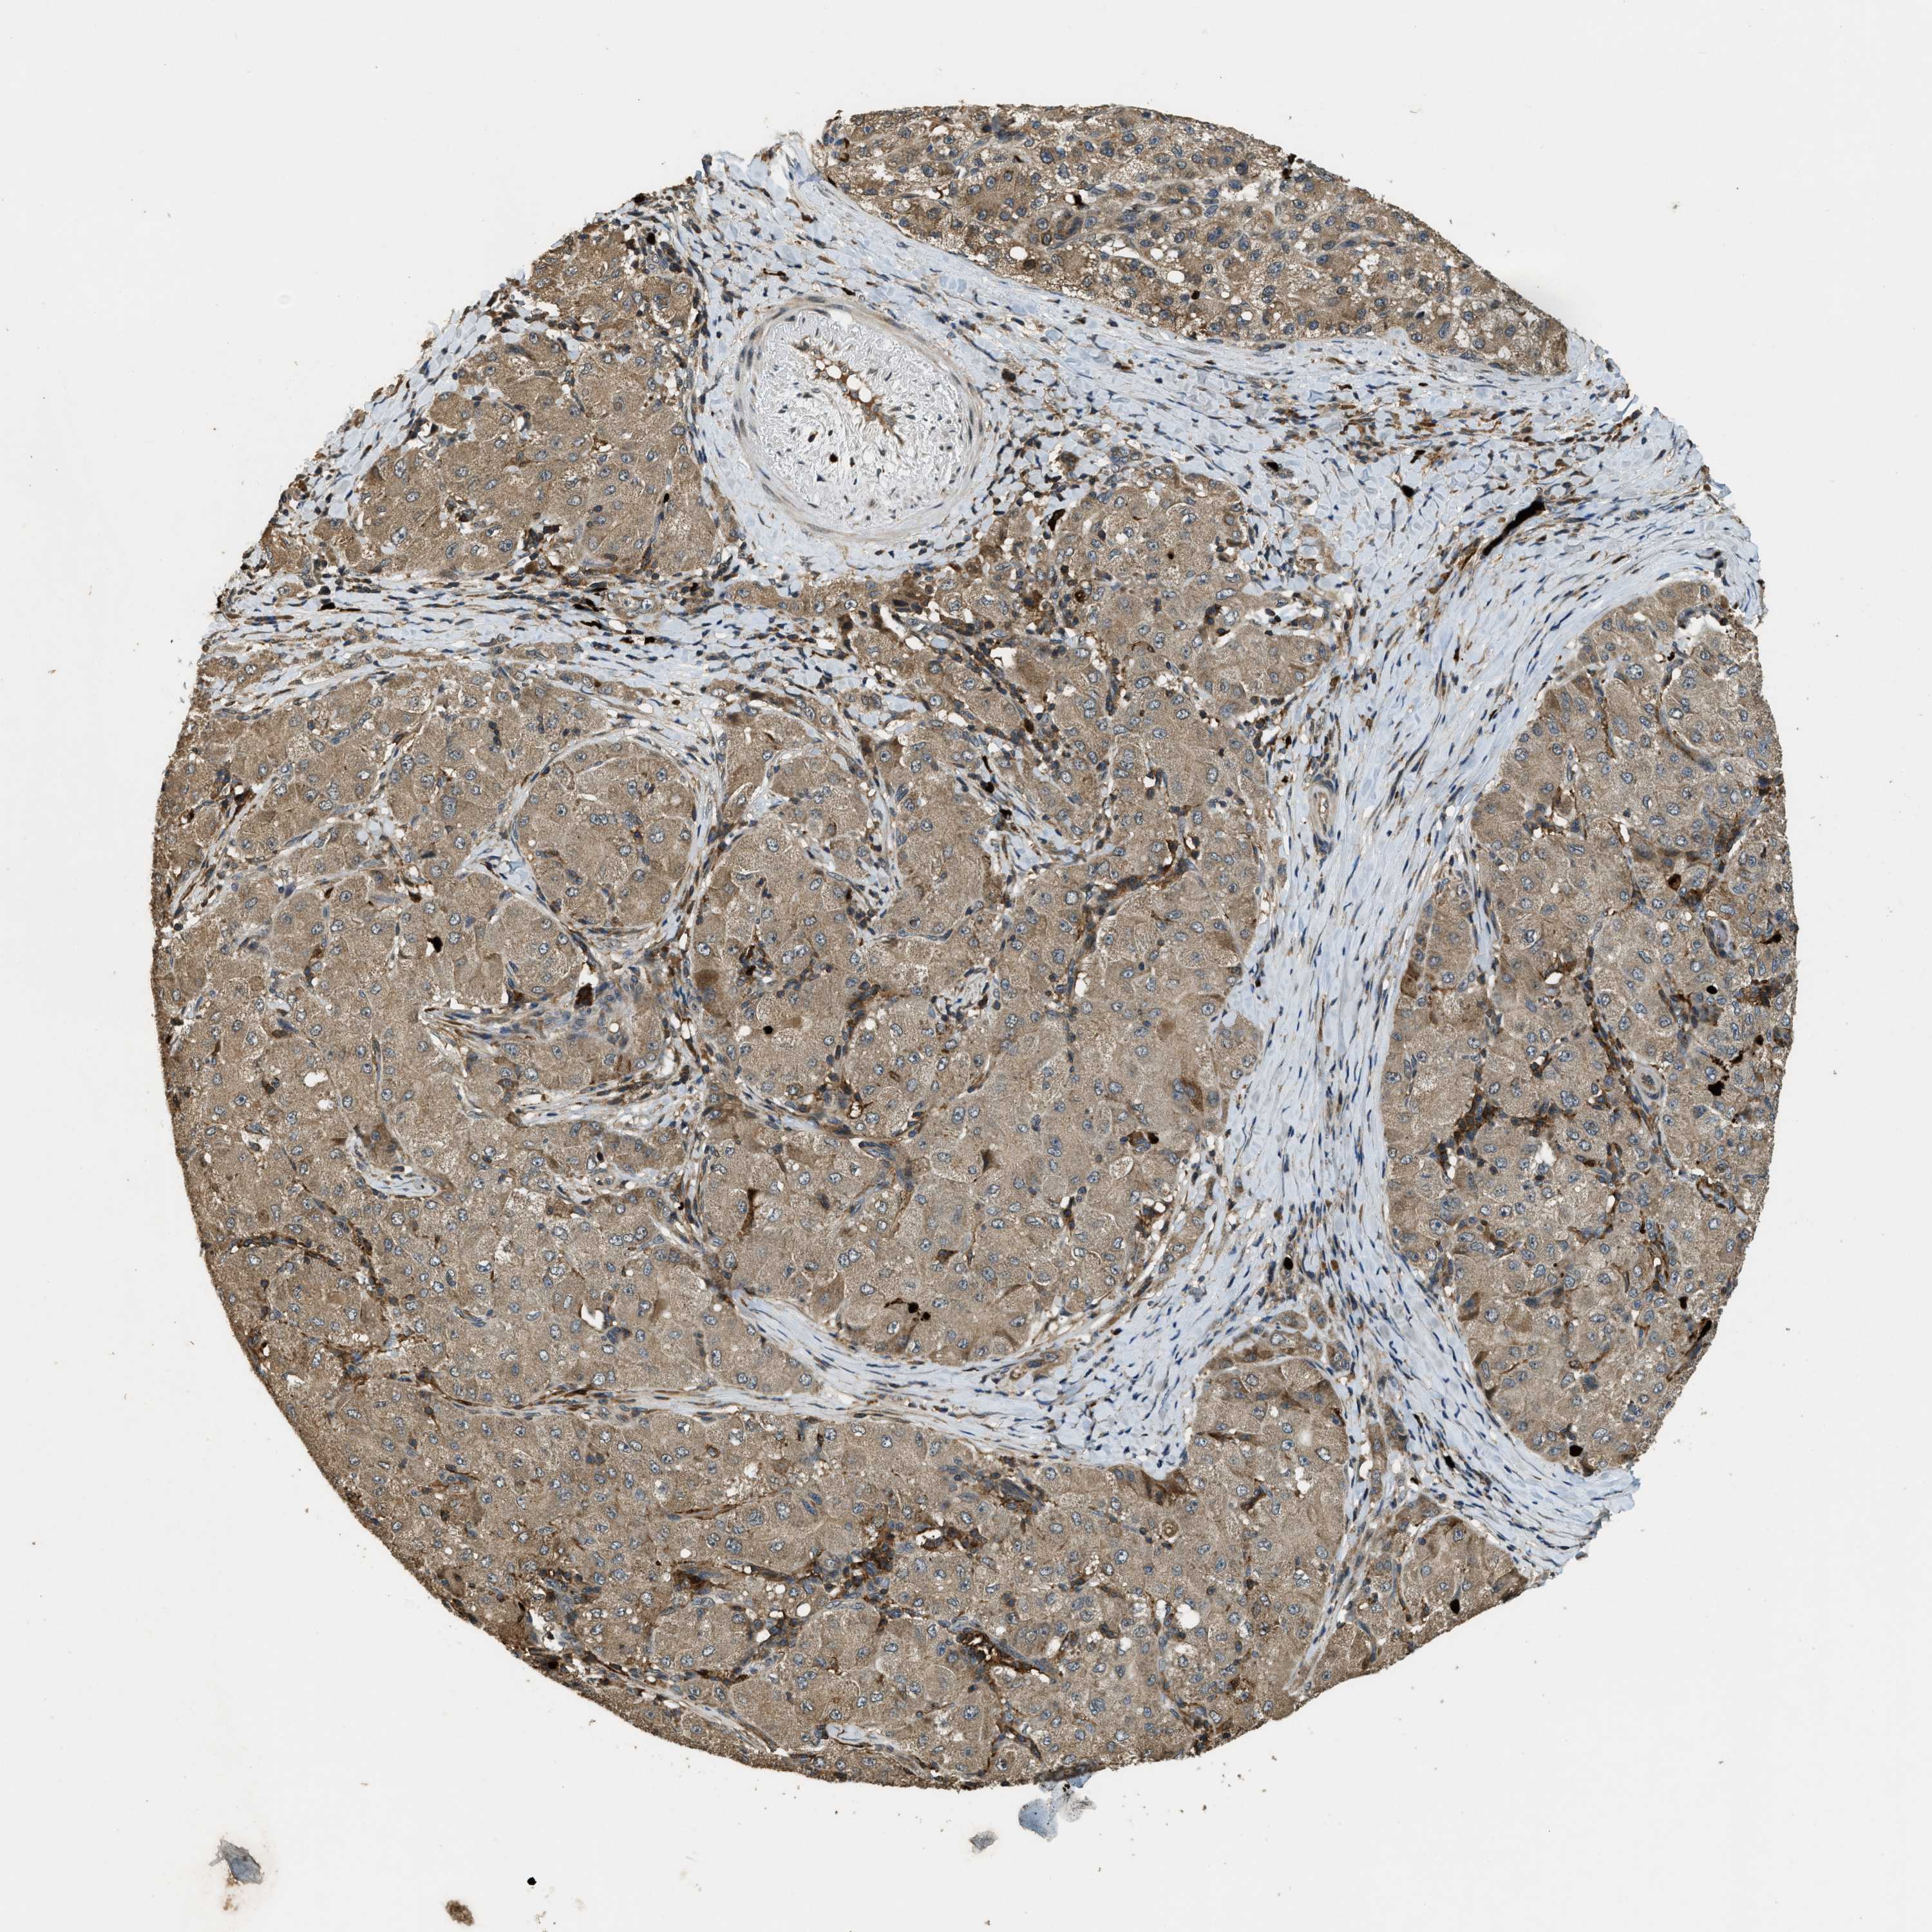

LIVER CANCER - Protein expressioni

A mouse-over function shows sample information and annotation data. Click on an image to view it in a full screen mode. Samples can be filtered based on level of antibody staining by selecting one or several of the following categories: high, medium, low and not detected. The assay and annotation is described here.

Note that samples used for immunohistochemistry by the Human Protein Atlas do not correspond to samples in the TCGA dataset.

Antibody stainingi

Antibody staining in the annotated cell types in the current human tissue is reported as not detected, low, medium, or high, based on conventional immunohistochemistry profiling in selected tissues. This score is based on the combination of the staining intensity and fraction of stained cells.

Each image is clickable and will lead to virtual microscopy that enables deeper exploration of all samples and also displays staining intensity scores, fraction scores and subcellular localization as well as patient and tissue information for each sample.

Antibody HPA018133

Staining

High

Medium

Low

Not detected

Intensity

Strong

Moderate

Weak

Negative

Quantity

>75%

75%-25%

<25%

None

Location

Nuclear

Cytoplasmic/membranous

Cytoplasmic/membranous,nuclear

Cholangiocarcinoma

Carcinoma, Hepatocellular, NOS